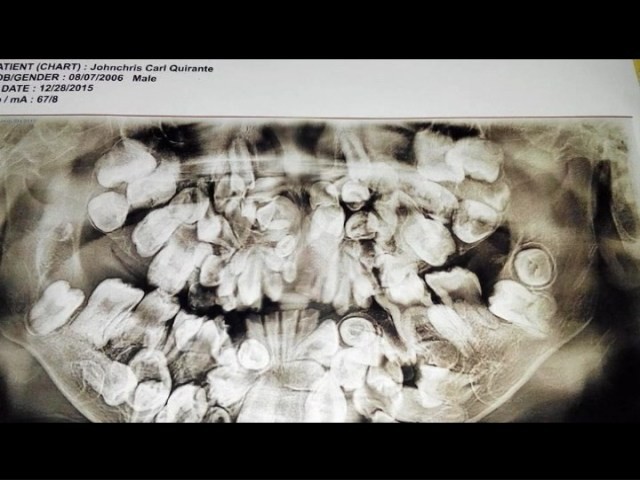

Cậu bé Johncris Carl Quirante hiện đang sống tại Barangay Looc, Dumanjog, Cebu, Philippines. Khi lên 2 tuổi, một điều bất thường đã xảy ra với hàm răng cậu bé, thay vì mọc 20 chiếc răng sữa như những đứa trẻ khác, Johncris lại có tới hơn 50 cái răng.

Cậu bé Johncris gặp phải tình trạng mọc thừa răng từ khi lên 2 tuổi.

Do điều kiện kinh tế nên bố mẹ Johncris không đưa cậu bé tới gặp nha sĩ. Nhưng tới khi cậu bé 5 tuổi thì số lượng răng đã lên tới 150 chiếc, lúc này Johncris mới được đi chụp X-quang lần đầu tiên. Trong vòng 4 năm tiếp theo, tình trạng tồi tệ hơn khi 300 chiếc răng mọc chen chúc trong miệng cậu bé.